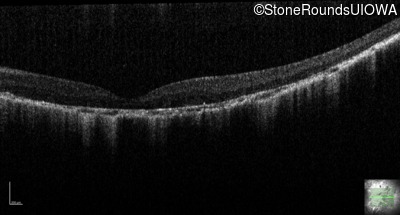

Optical Coherence Tomography - Right - 20/200 +1

Exemplar / OCT Stack